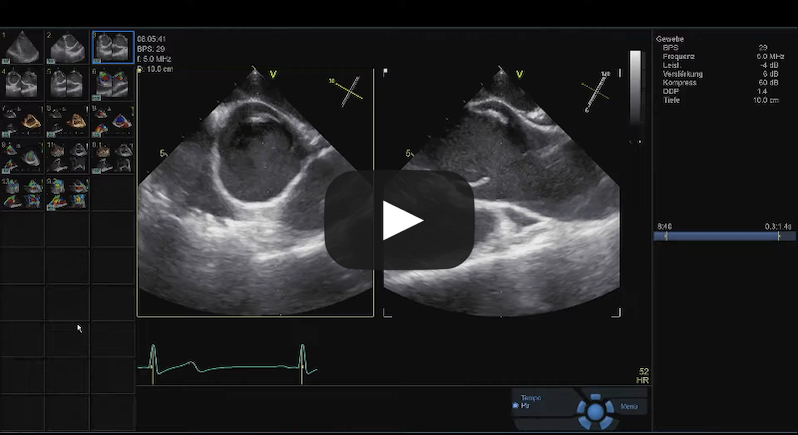

Bicuspid Aortic Valve Repair

Source: Cardiac Research & Education Saar GmbH, used with permission.

Tricuspid Aortic Valve Repair